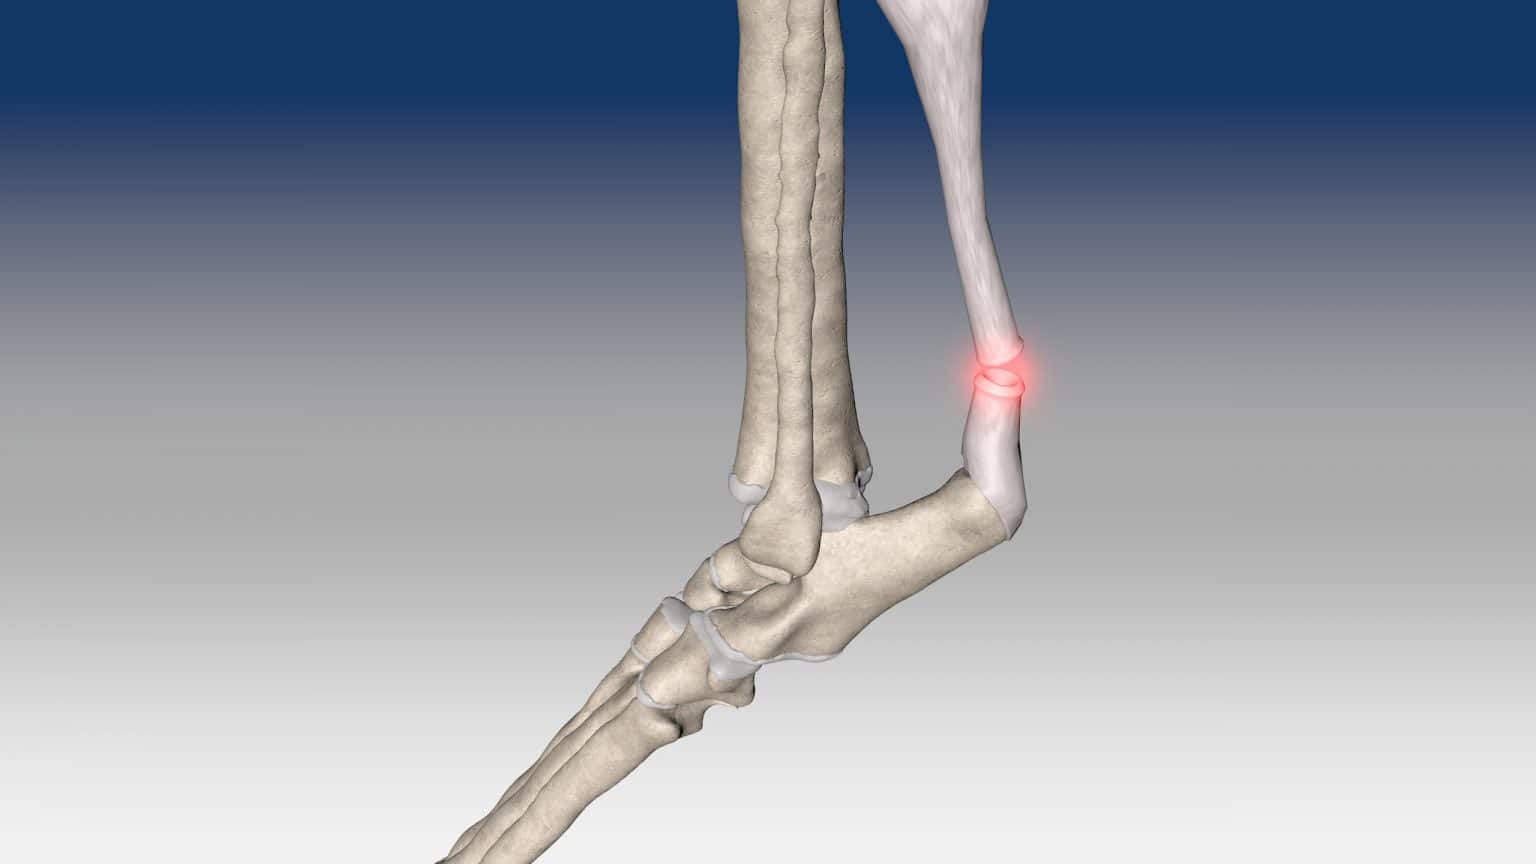

Achilles Tendon Repair